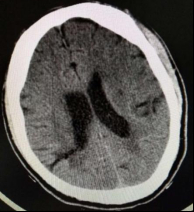

患者于当日23:50送达本院急诊抢救室。来院时神志不清,GCS评分7分,血压132/87 mmHg(1 mmHg=0.133 kPa),心率90次/min,呼吸22次/min,脉搏92次/min,血氧饱和度96%,血糖6.7 mmol/L。查体见面色红润,舌体咬破。两肺呼吸音清,未闻及干湿性啰音,心律齐,无明显病理性杂音,腹平软,压痛反跳痛难以配合,两侧病理征未引出。2019-01-02 23:58心电图示窦性心律,ST段改变(图 1A)。2 h后复查心电图示窦性心动过缓,ST-T改变,左室高电压、心电轴左偏,Ⅰ、Ⅴ5、Ⅴ6导联ST段呈水平型、下斜型压低,0.05~0.1 mV,Ⅴ1、Ⅴ2、AVR呈水平型抬高(图 1B)。(2019-01-03 00:15)床边检测cTnT 0.014 ng/mL,D-二聚体 > 10 000 ng/mL,NT-pro BNP 20 600 ng/L。2 h后复查cTnI 0.049 ng/mL。生化示肌酐284 μmol/L,其余指标未见明显异常。头颅CT示右侧颞枕叶条片灶,局部似与右侧脑室后角相连,脑裂畸形:合并灰质异位?软化灶合并脑穿通畸形?(图 2)。胸部CT示心脏增大、肺动脉高压,肺动脉主干增宽4.0 cm,心包前部少许积液。床边心超示:左室壁运动欠协调,室间隔运动稍减弱,主动脉瓣反流(轻度),EF为52%。患者入院后烦躁不安,先后予镇静、抗癫痫等治疗。因患者D-二聚体升高明显,胸部CT示肺动脉增宽明显、肺动脉高压,考虑存在肺栓塞可能; 另一方面,患者血压呈进行性上升,D-二聚体升高,CT示心包前部少许积液,故主动脉夹层亦不能除外,需行动脉造影明确,但因患者肌酐异常,存在慢性肾衰竭,行增强CT检查需注射造影剂,可能进一步加重肾损害,故家属拒绝。2019-01-03 07:00患者神志转清,诉有头晕,无胸痛,血压持续波动在200/100 mmHg左右,予镇静、降压效果均较差,病情反复告知家属,家属商议后最终同意行CTA检查。13:05行胸部增强+肺CTA示主动脉弓夹层(De Bakey I、Stanford A型),肺动脉高压(图 3)。最终患者诊断主动脉夹层(De Bakey I、Stanford A型)明确,因本院手术条件所限,当天即予转上一级医院手术治疗。

| 图 2 患者头颅CT图像(右侧颞枕叶条片灶) |

本病例的诊断上存在干扰因素较多,容易有以下五个误区。误区一:易误诊为急性冠脉综合征。胸闷、心电图ST-T改变,加上高血压、糖尿病病史,接诊医生极易诊断为“急性冠脉综合征”,因基层医院条件所限无法完善心肌酶谱检查,更无法完成血管造影检查,所以导致了初步诊断的误诊。这也提示单凭主诉与心电图来诊断急性冠脉综合征是不严谨的。此外,心电图的缺血表现提示该患者冠脉可能有受累,但因患者未行PCI检查使得无法证实。误区二:易误诊为一般的癫痫或阿-斯综合征发作。患者癫痫样发作后来本院查头颅CT提示右侧颞枕叶存在条片状异常,且后来患者神志转清,故本院接诊医生考虑存在颞叶癫痫可能; 另一方面,予动态复查心电图、心肌酶谱存在异常,因此需与急性冠脉综合征所致阿-斯综合征发作相鉴别。有报道,部分病例中可将癫痫发作作为诊断脑梗死的首要依据[7]; 本病例考虑为夹层撕裂累及头臂干后致大脑循环低灌注,引起缺血性卒中,从而继发早发性癫痫。误区三:易误诊为肺栓塞。胸闷、D-二聚体升高明显、肺动脉明显增宽、肺动脉高压等特点,均提示存在肺栓塞可能,值班医生一度考虑急性肺栓塞并动员家属行肺动脉CTA检查。但患者血气未见低氧血症、心超未见右心增大、难以解释的癫痫样发作,诊断肺栓塞依据不充分,CTA检查可排除。提示对于存在肺动脉增宽伴肺动脉高压的患者,除考虑肺栓塞外,还要排除主动脉夹层。误区四:易受肌酐影响而放弃行CTA检查。该患者肌酐异常,存在慢性肾衰竭,行血管造影可能加重肾损伤,存在诱发造影剂肾病的风险[8]。若值班医生未多次劝说家属行CTA检查,该病例可能仍处在误诊之中,甚至在还未行CTA检查时患者就急性加重死亡,引起医疗纠纷。误区五:易漏诊主动脉夹层。该患者发病时无明显胸痛、背痛等典型的撕裂样疼痛,两侧桡动脉对称、心超未见假腔,极易漏诊,回顾病史,患者的血压持续处于高水平,结合D-二聚体及CT提示心包前部少许积液及肺动脉增宽,诊断主动脉夹层已有迹可循。这也说明床旁心脏超声在主动脉夹层诊断中的应用存在假阴性,临床医师在诊断此类疾病时需引起重视。